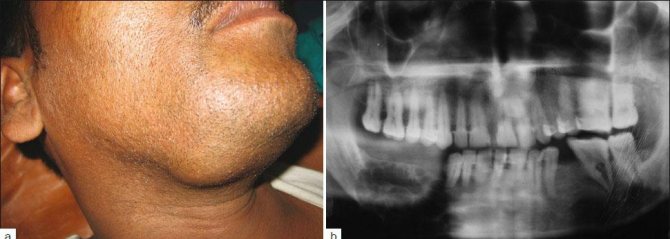

Внешний вид пациента с амелобластомой нижней челюсти.

Во время первого визита больного к стоматологу специалист обращает внимание на специфическое уплотнение челюсти, что искажает внешний вид пациента. Кожный покров в области патологического новообразования сохраняет свой естественный цвет и легко собирается в складку.

Асимметрия пациента с амелобластомой нижней челюсти

- Рентгенография. На рентгенологическом снимке опухоль проявляется множественными округлыми полостями в костной ткани челюсти, разделенных отдельными перегородками.

Рентгенологический снимок амлобластомного поражения нижней челюсти